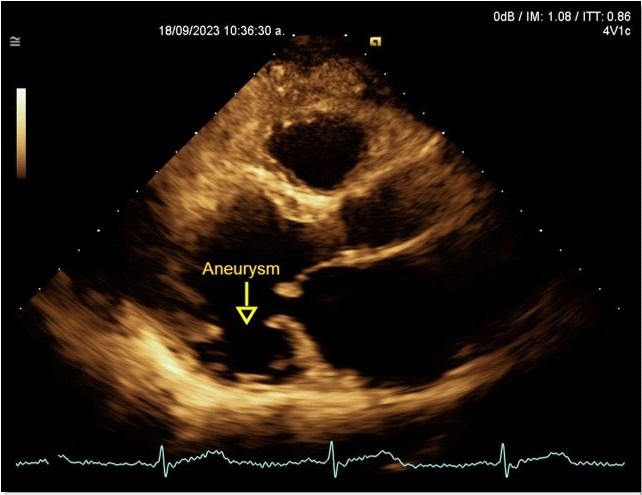

A transthoracic echocardiogram revealed dilated, possibly Chagas-related cardiomyopathy due to an aneurysm involving two segments (basal inferolateral and basal anterolateral), with an aneurysm-to-mouth width ratio of 0.45; the remaining mobility was normal. The LV had an enlarged diameter, eccentric hypertrophy and a 49% LVEF. The mechanism of severe MR was secondary to annular dysfunction due to the aneurysm, in addition mitral annulus dilation and asymmetric tenting of the posterior leaflet, resulted in a wide, eccentric, and complex jet with a Coanda effect. The probability of pulmonary hypertension was low, with a pulmonary artery systolic pressure of 32 mmHg (Fig. 6, 7).

Figure 6. Echocardiogram, parasternal long-axis view: Basal inferior-lateral aneurysm, aneurysm-to-mouth width ratio – 0.45 (Yellow arrow)